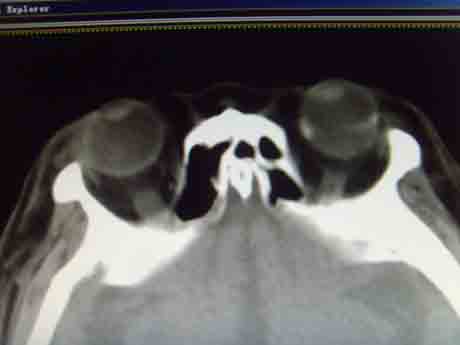

CT50843:左侧眼球钙化诊断什么?

左侧眼球钙化诊断什么?

左侧眼球内见不规则钙化,视网膜母细胞瘤不排除。

患者年龄?成人考虑脉络膜骨瘤。

建议除外视网膜母细胞瘤